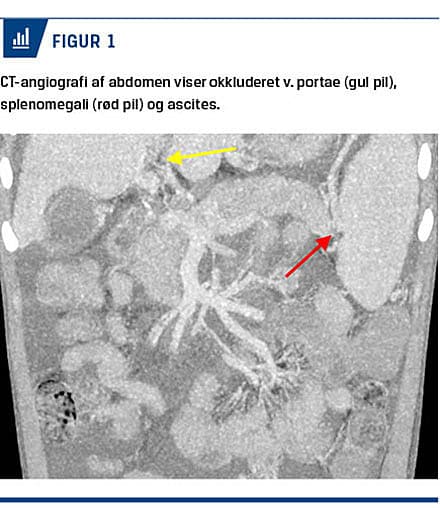

En CT-angiografi af abdomen viste obliteret vena porta med udtalte kollateraler og betydelig splenomegali (13 cm) (Figur 1). I dagene efter den primære banding var der flere episoder med reblødning. Patienten blev behandlet efter gældende retningslinjer med terlipressin, Sengstakensonde og gastroskopi med banding. Pga. fortsat ukontrollabel blødning blev han splenektomeret, hvorefter tilstanden blev stabiliseret. Han blev udredt for portal hypertension og leversygdom (Tabel 1), men der blev ikke fundet nogle årsager fraset trombosering af vena porta på grund af NVK i neonatalperioden.